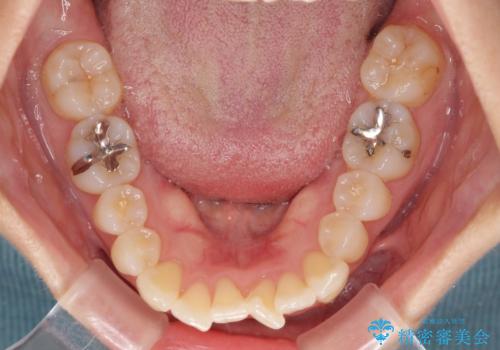

- 前歯の捻れと、それに伴う口元の突出感を気にして来院された患者様です。

早く治療を終えたいとのことで、ワイヤー装置による矯正治療を行うこととしました。

上顎前歯の叢生が解消されると出っ歯になることが分かっていたので、両側奥歯付近にアンカースクリューを入れ、出っ歯を改善するためのゴムかけを行いました。